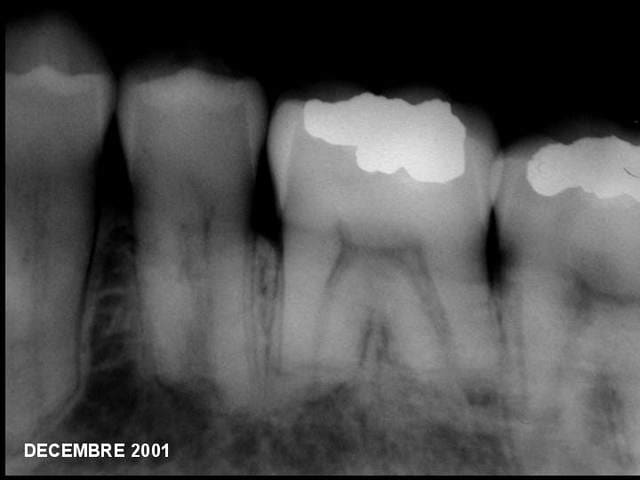

> Donc le cas :

>

> Patient :

> . Homme, 41 ans,

> . Ayant subi une exérèse d’améloblastomes

> mandibulaires bi-latéraux 13 semaines auparavant,

> . Présentant une légère paresthésie bi-latérale

> et réponses négatives aux tests thermiques et

> électrique des dents n° 34, 35, 36, 37, 46, et 47,

> . Percussion négative sur toutes ces dents.

> Quel(s) traitement(s) envisageriez-vous pour ces

> dents ?

Bon c'est bientôt Noël, et comme j'ai eu la réponse, je vous la fournis en (presque) direct live.

L'argumentaire devrait suivre dans la journée.

Réponse :

Aucun traitement n’était nécessaire.

24 mois plus tard :

. La cicatrisation osseuse est complète;

. Toutes les dents ont retrouvé des sensibilités normales (chaud, froid, percussion)

. Les paresthésies ont disparu.

P.S bravo à athos et guttaman pour leur sagacité. al tu es nul, je le dis publiquement :)